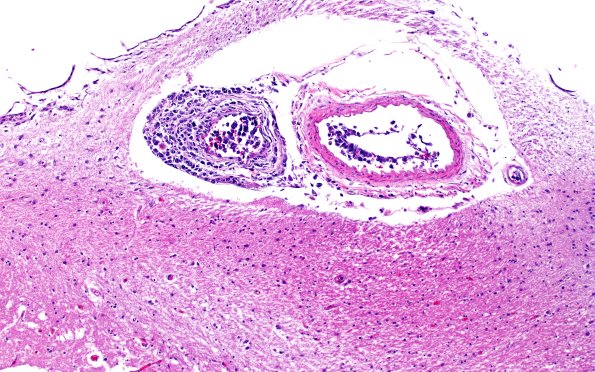

Washington University Experience | NEOPLASMS (HEMATOLYMPHOID) | Lymphoma, Intravascular | 18D1 Lymphoma, intravascular N4 (Case 18) 10X

18D1,2 This interesting arteriole/venule pair (shown by an arrow in image #18C1) demonstrates luminal growth in the artery but is invading through the vessel wall in the vein. (H&E)